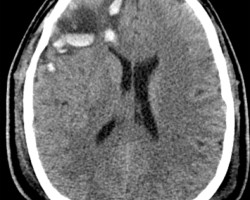

- Radiographic findings consistent with TBI:

- Skull fractures

- Cerebral contusions, typically in areas where brain parenchyma rubs against skull bone (i.e. inferior temporal and frontal lobes)

- Cerebra edema

Diffuse axonal injury

- Due to shearing forces from extreme acceleration and deceleration.

- A biopsy will have swollen proximal ends of axons in the appearance of bulbs known as “retraction balls.” Punctate hemorrhages may also be seen.